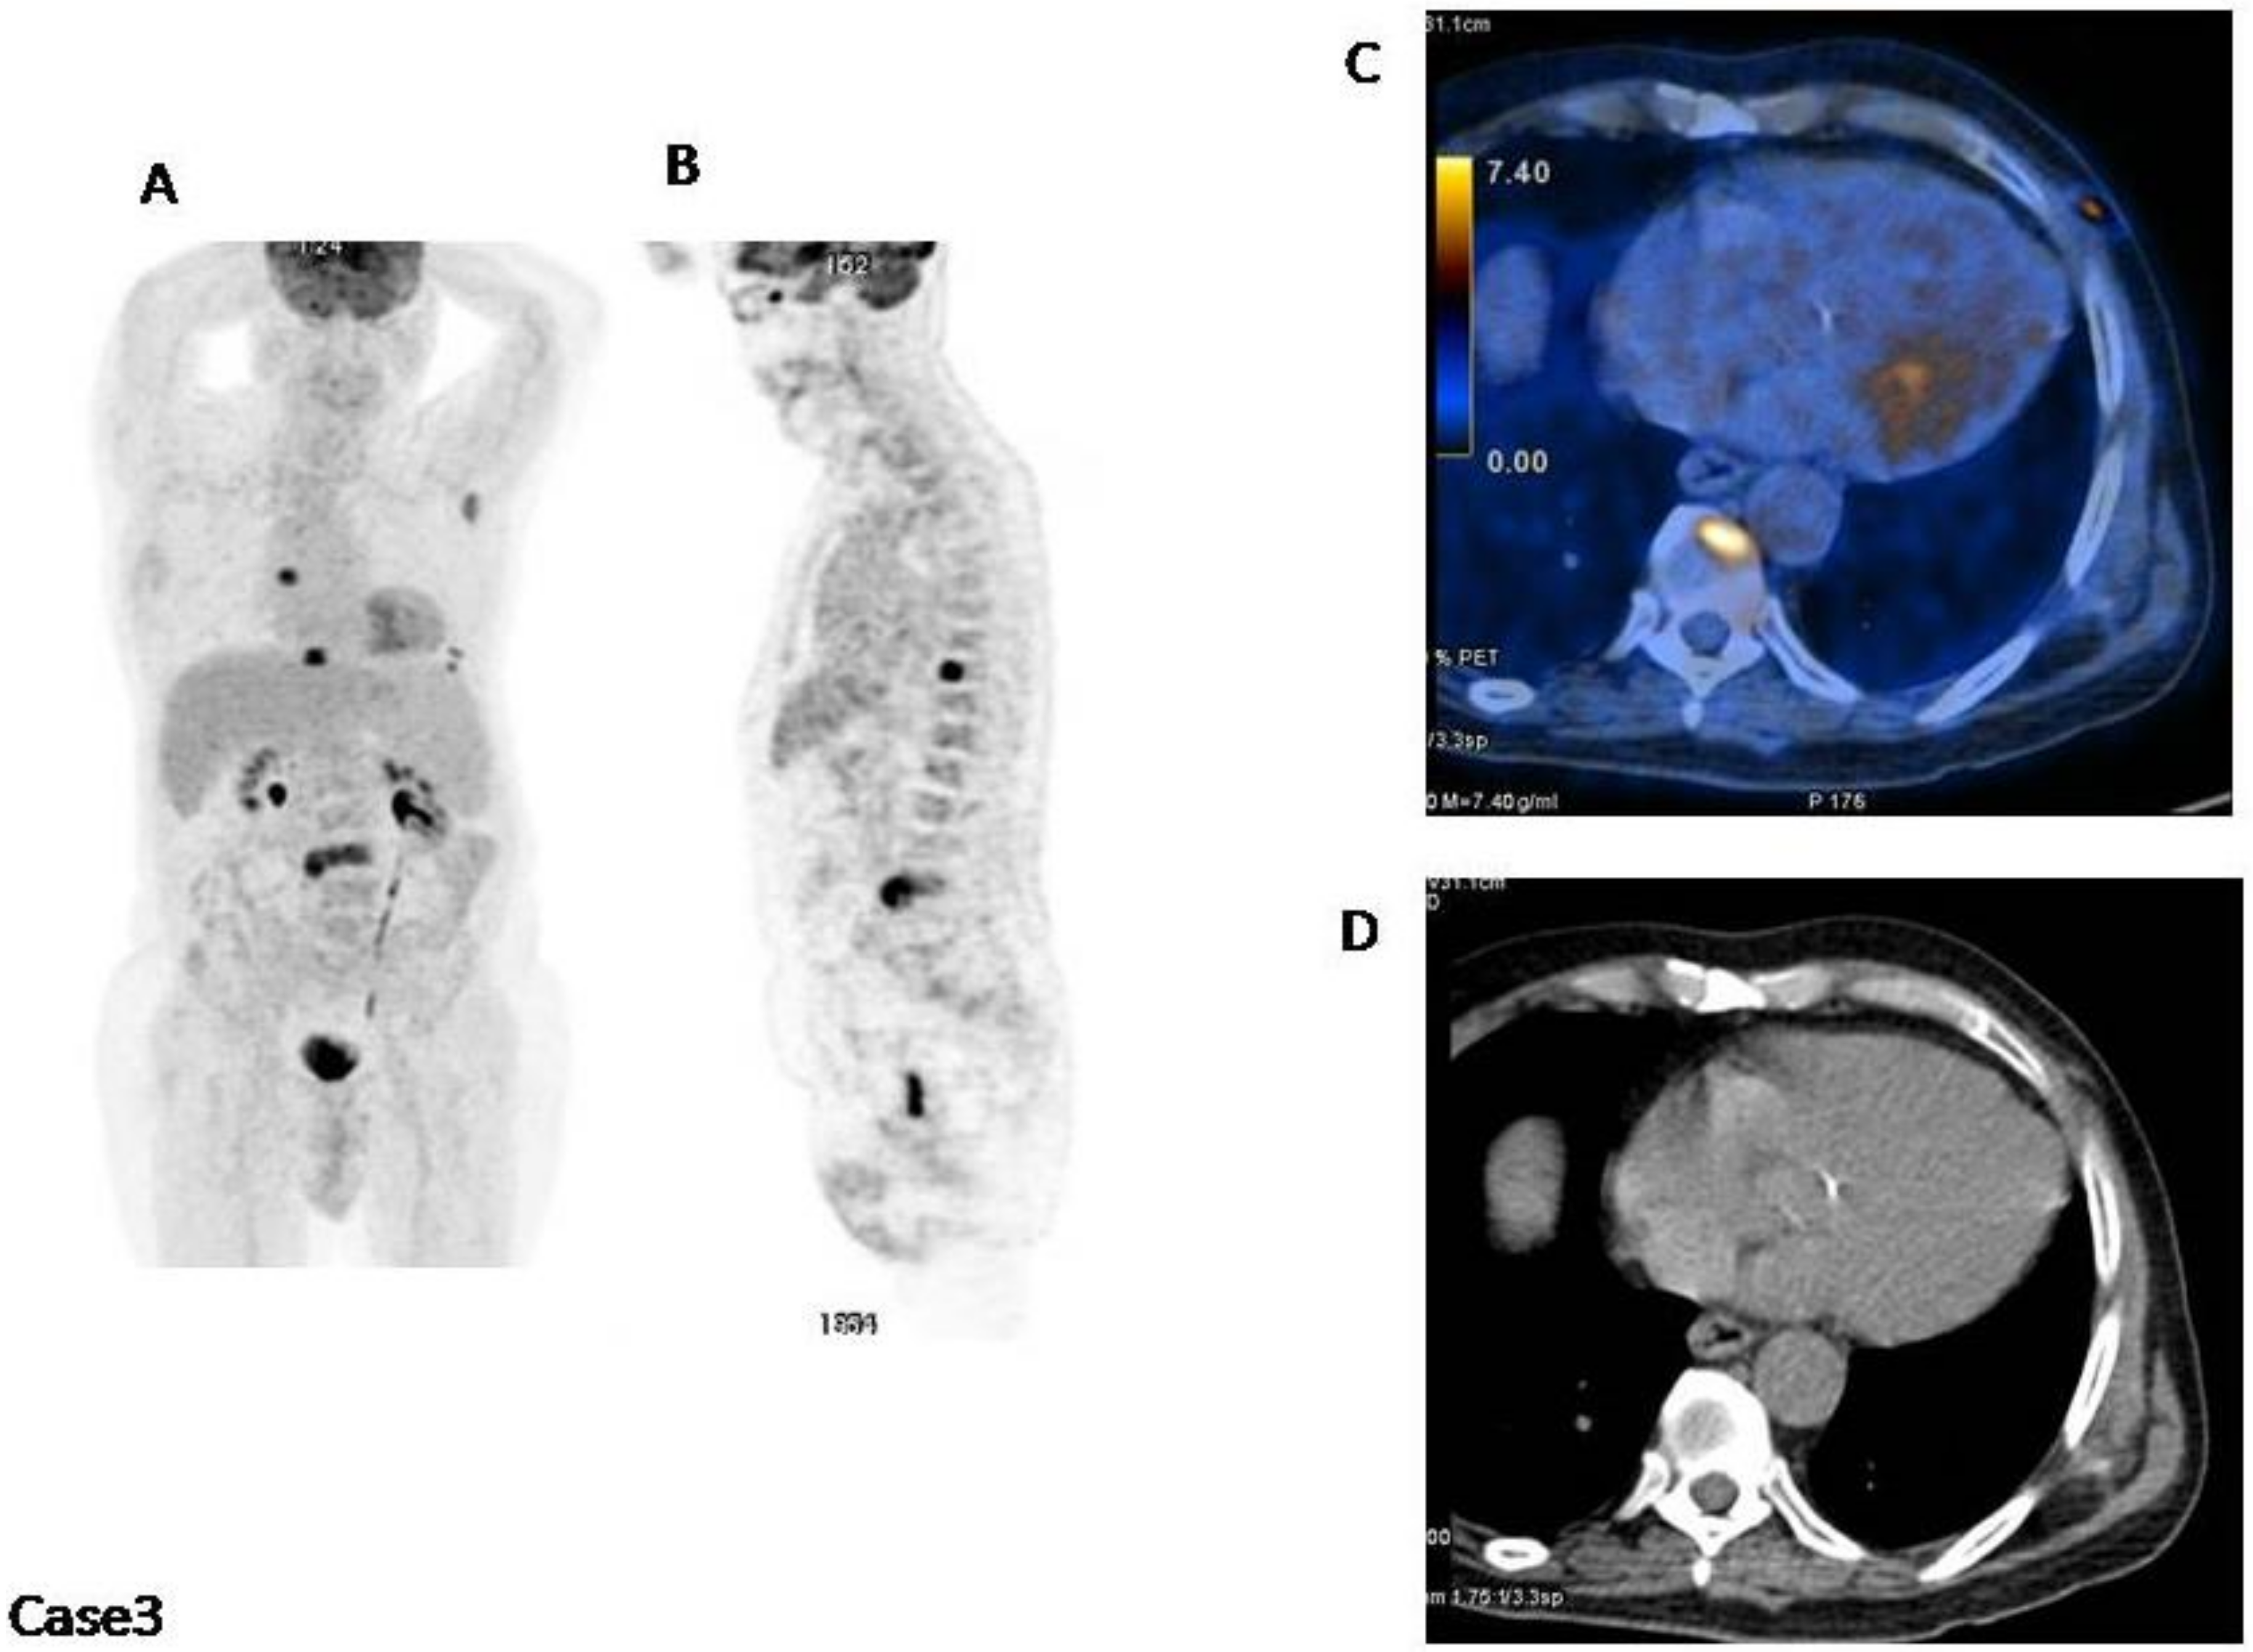

4. Impetus Criteria: Examples of Application